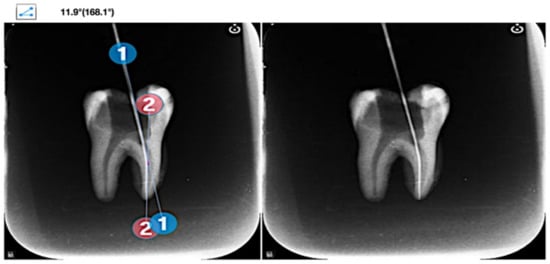

- Schneider, S.W. A comparison of canal preparations in straight and curved root canals. Oral Sur. Oral Med. Oral Pathol. 1971, 32, 271–275. [Google Scholar] [CrossRef]

- Zhang, R.; Hu, T. Root canal curvature. Int. Endod. J. 2010, 43, 616–618. [Google Scholar] [CrossRef]